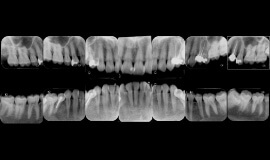

デンタルレントゲン

一般的な「パノラマレントゲン」だけでなく、かみ合わせや歯並びを診る「セファロ」、一本単位の診断のための「デンタル」、そして炎症の広がりを診たり、歯根の病気の確定診断に使用する「CT」を撮影します。